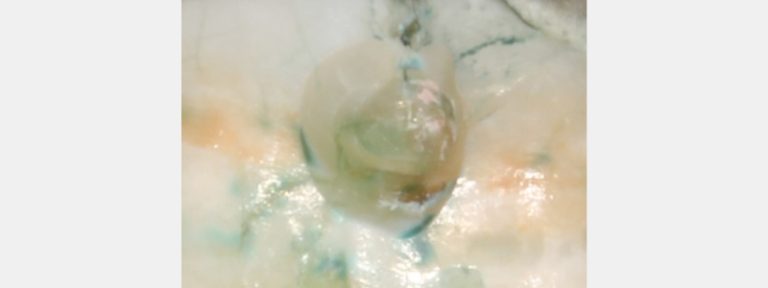

Caries detection dyes help dentists determine when to stop tooth preparations in conservative treatment.